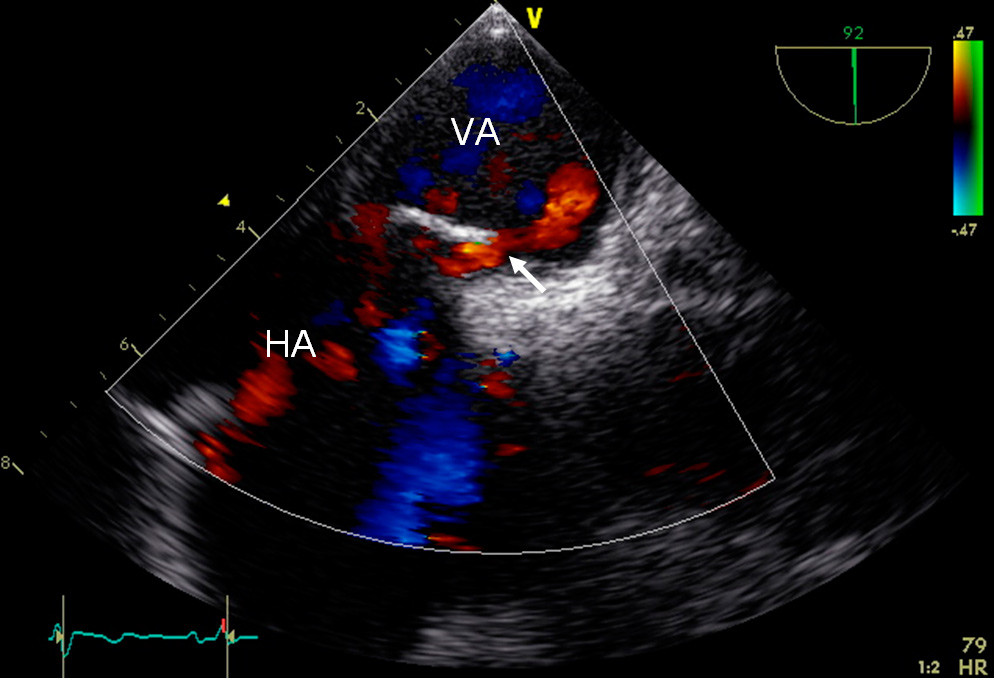

Cerebral computertomografi (CT) utført ved lokalsykehuset viste «hyperdens høyre a. cerebri media-tegn», og cerebral CT-angiografi viste en embolisk okklusjon i delingen av høyre a. cerebri media. Cerebral CT dagen etter dokumenterte infarkt i basalgangliene i høyre hemisfære, og CT-angiografi viste fullstendig rekanalisering av høyre a. cerebri media. Transøsofageal ekkokardiografi med saltvannskontrast to dager etter innleggelsen viste åpent foramen ovale med diameter på 4 mm (fig 1).

Transøsofageal ekkokardiografi med saltvannskontrast er gullstandard for diagnostisering for høyre-venstre-shunt (25, 26). Med denne undersøkelsen kan åpent foramen ovale visualiseres og shunten diagnostiseres ved påvisning av mikrobobler under Valsalva-manøver i venstre atrium innen tre til fire hjerteslag etter saltvannsinjeksjon i en vene (17, 27).